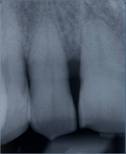

Fig 11

Radiographic re-evaluation 6 months from surgery

Int J Med Sci Image

At 9 months from the procedure the dental elements were virtually stables, with a mean gCAL (gain hi clinical attachment) of 2.6mm; radiographic evaluation showed defect filling and good prognosis [fig. 12-13].